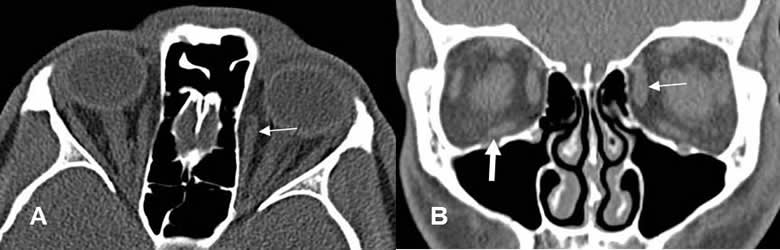

Fig 216. Fractura de órbita, con atrapamiento muscular.

A y B: TAC reconstrucción coronal. Fracturas en el piso de la órbita. Los músculos rectos inferiores están redondeados, por edema y desplazados inferiormente, signos de atrapamiento.

Fig 217. Fractura de órbita.

TAC reconstrucción coronal. Fractura no desplazada en el borde lateral de la órbita.